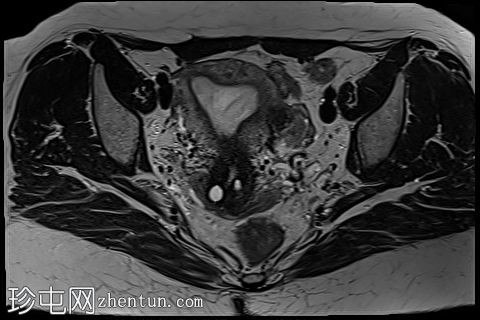

冠状位

STIR序列

4.jpg

左侧卵巢可见数个小囊肿,在T1加权像上呈高信号,在T2加权像上呈低信号(T2阴影),T1脂肪抑制序列未见信号下降,提示其为血液降解产物。最大的囊肿轴位大小约为3.1×1.7 cm,轻度压迫卵巢实质。

边界模糊不清是局灶性子宫腺肌症(无包膜)的特征。此外,病灶内存在多个微小的内部出血灶(异位腺体),且邻近增厚模糊的交界区,这些都是局灶性子宫腺肌症的诊断标准。

一种罕见的变异型是囊性腺肌症,据信是由反复的局灶性出血导致囊腔内充满变质血液成分所致。

少数左侧卵巢囊肿伴有上述出血信号,可能代表子宫内膜异位囊肿,因为多发性和双侧性更倾向于子宫内膜异位囊肿而非出血性囊肿。